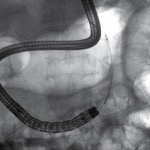

In this month’s column, I highlight articles related to training and quality in endoscopic ultrasound. EUS indications have rapidly evolved with more complex interventions. Therefore, it is important that we look at the quality of what we do and how we train the next generation of endosonographers. Training in one EUS procedure does not imply competence in another.

This month’s second featured article is a review on the state of EUS training that discusses resources available worldwide, different training models, limitations, and challenges.

The ACG and ASGE have updated their quality indicators for EUS in response to new evidence and innovations in EUS use, including the growth of interventional EUS, over the past decade.

An international team of investigators has outlined the current state of EUS training and highlighted strengths and limitations of current training models. Given the technical challenges of EUS and expansion of its use from diagnostic to interventional applications, the authors emphasized the need for training centers and standards that promote expertise in “both theoretical knowledge and practical procedures.”